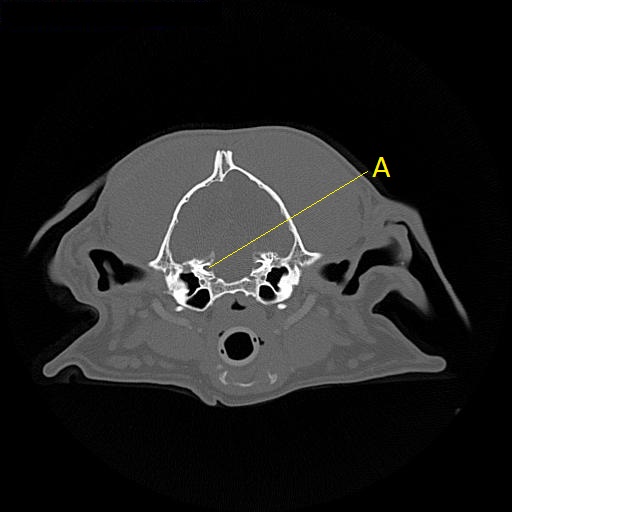

Q. Identify the structure labeled below:

A. Canal for the trigeminal nerve